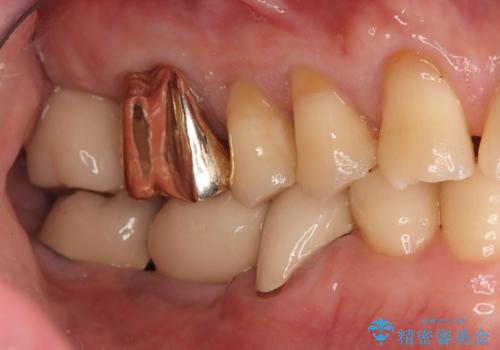

●審美性の維持

特に前歯部では、抜歯即時インプラントによって歯肉形態や骨形態が維持されやすく、審美的な結果につながる。

●手術回数の削減

抜歯と埋入を同日に行うため、患者の外科的侵襲が1回で済み、身体的・心理的負担が軽減される。